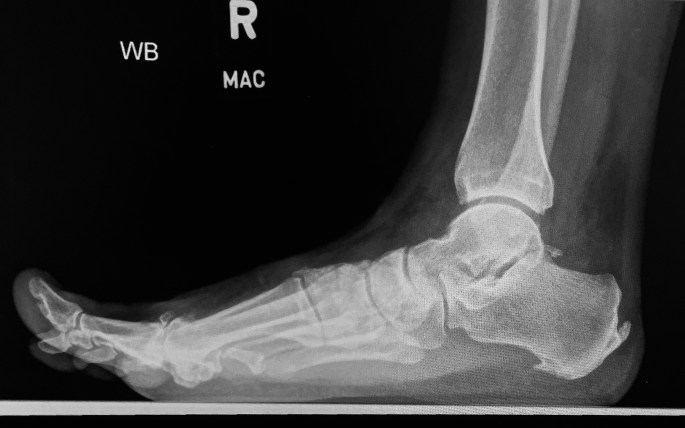

This is a Lateral view of a painful arch, Right foot.

“This is a radiograph of the right foot, Lateral view. With Achilles tendon insertion, and plantar fascia origin enthesophyte (spurring). There is a break in the anterior cyme line, and dorsal spurring of the 1st metatarsal head. The dorsiflexed toe shows limited range of motion.

My impression is… consistent with image 1, Hallux Rigidus with metatarsal head flattening, dorsal spurring, and decreased first metatarsal joint range of motion. Regnauld/Oloff classification Stage 3. ”

Answer: Hallux Rigidus